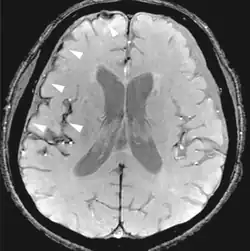

Fluid-attenuated inversion recovery FLAIR Fluid suppression by setting an inversion time that nulls fluids High signal in lacunar infarction, multiple sclerosis (MS) plaques, subarachnoid haemorrhage and meningitis (pictured).[78]